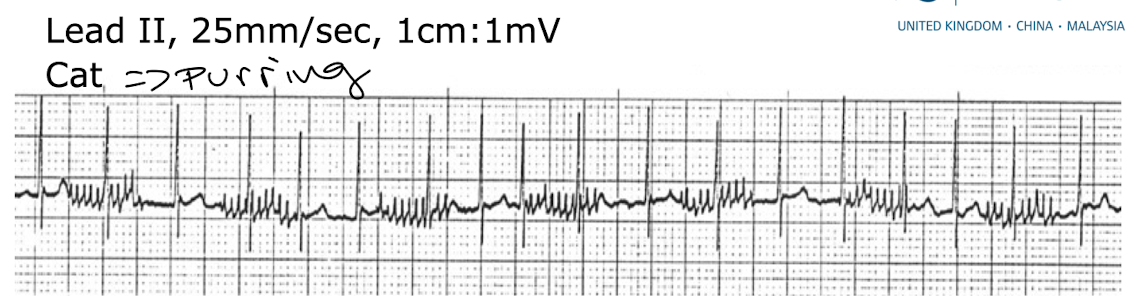

Q

what is causing this baseline interference

A

muscle tremor (purring of cat)